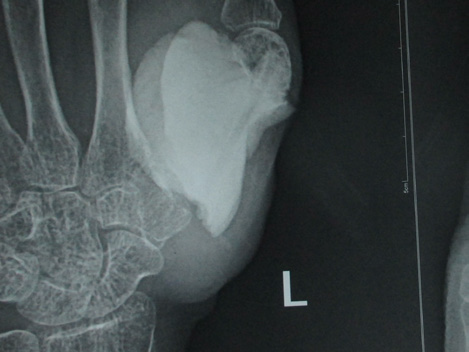

In November 2015 one 60 years lady presented in a newly recognised Medical College of eastern India (Murshidabad Medical College) with recurrence of GCT of the 1st MC of left hand and soft tissue involvement. One year back she was presented in another medical college with intraosseous Capancci grade III lesion of the same site of two years duration where it was treated with narrow margin resection, interposition bone cement on a Kirschner wire (K wire) (Figure 1). It started recurring after 8 months of resection. But presented to us after another one year when extensive extension within soft tissue took place. In plain x ray one small osteolytic lesion was noticed over mid shaft of second metacarpal of the same hand which was not seen in earlier radiographs. MRI was done to identify adjacent bone involvement and to know extent of the lesion in soft tissue (Figure 2). Involvement of regional lymph node and lung metastasis were excluded clinically and radiologically.

Figure 2 a. Clinical picture on presentation one year after recurrence; b. X-ray at that time showing soft tissue and second MC involvement; c & d. MRI show similar findings but without involvement of major nerve and vessels.